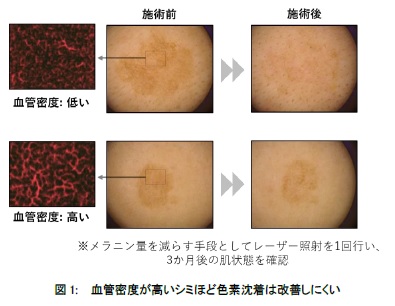

資生堂、シミ部位の血管密度が色素沈着の改善に影響することを発見株式会社資生堂のプレスリリース。